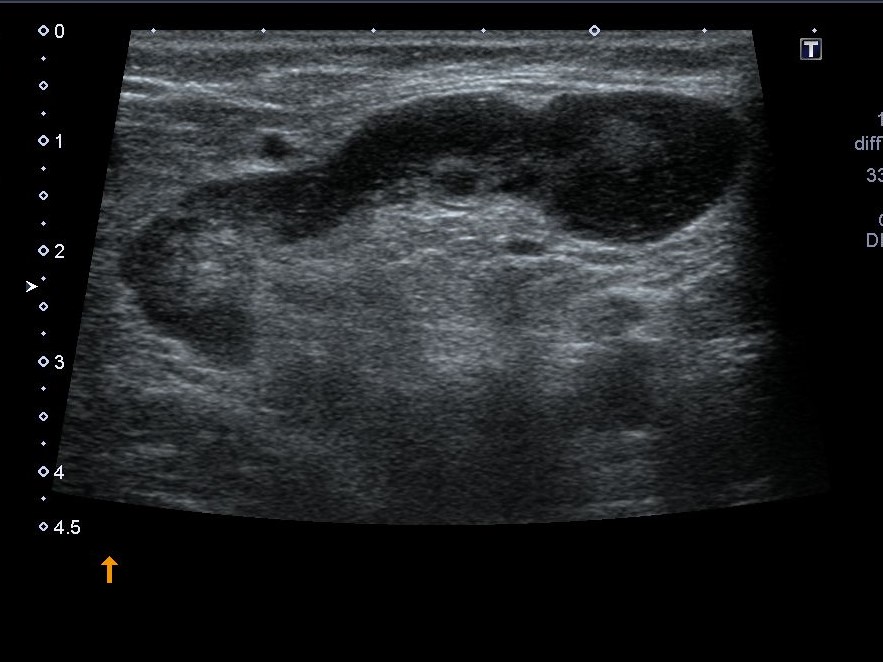

Мезентериальные лимфатические узлы: УЗИ и диагностика